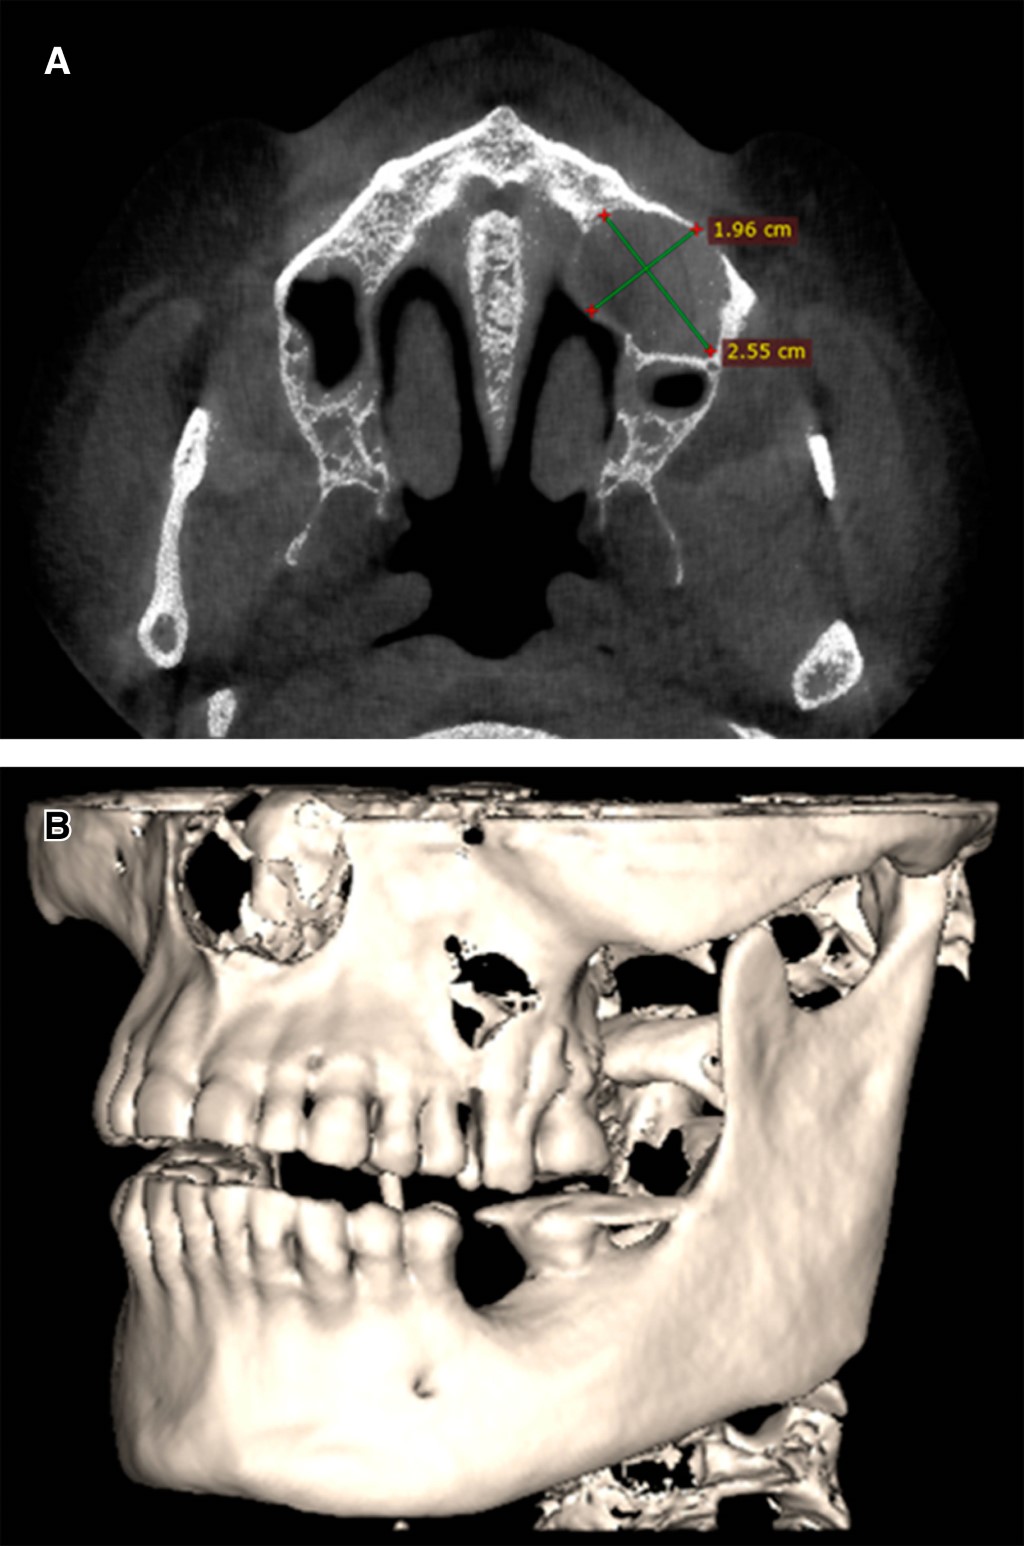

Reporte de caso inusual de queratoquiste odontogénico esporádico maxilar

El queratoquiste odontogénico (OKCs) es una enfermedad rara que se manifiesta en la región maxilofacial, afecta principalmente a la mandíbula más que al maxilar y se asocia con la presencia de un diente retenido. La mayoría de los casos son asintomáticos, afecta más a hombres que a mujeres en su segunda década de vida; los pacientes pueden presentar dolor o hinchazón de tejidos blandos en los OKCs infectados. La expansión ósea y la parestesia de los labios se registran en menos casos. La región más común en los maxilares es el tercer molar y la región canina. El objetivo de este informe es presentar un caso clínico infrecuente de un varón de 72 años con CCO asintomáticos en región maxilar izquierda, que presenta lisis ósea en región vestibular y palatina con aleación de fosas nasales sin comprometer los dientes. El paciente fue tratado con enucleación y osteotomía periférica mediante instrumento rotatorio; actualmente sin recidiva. También se realiza una revisión de casos con queratoquiste maxilar.

Figura 3

Figura 4